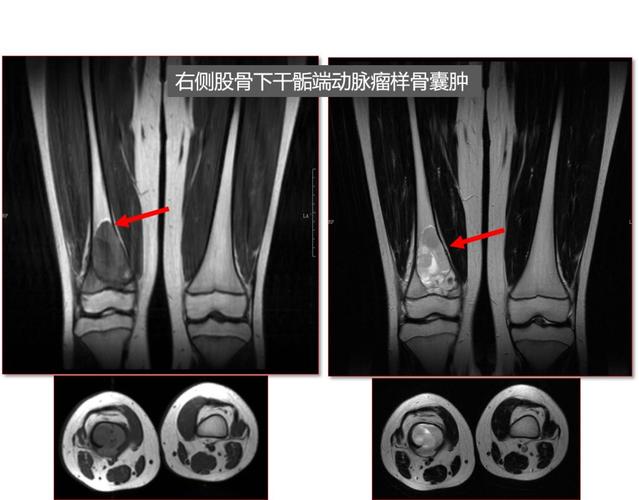

动脉瘤样骨囊肿(abc)

动脉瘤样骨囊肿影像

动脉瘤样骨囊肿图片

动脉瘤样骨囊肿ct表现

胫骨动脉瘤样骨囊肿